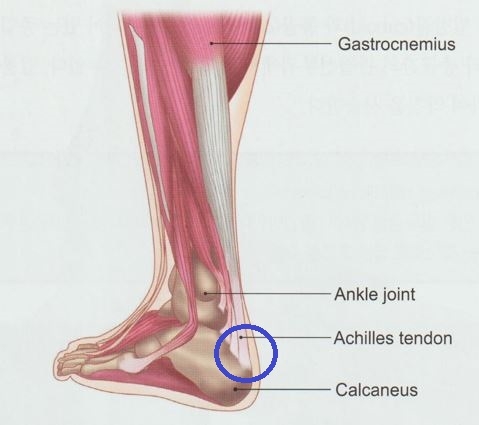

아킬레스건은 종아리 근육인 비복근과 가자미근에서 시작하여 종골에 부착되는 매우 강한 힘줄로, 인체에서 가장 큰 건에 해당합니다. 아킬레스건의 손상은 크게 건염과 건파열로 구분할 수 있습니다.

아킬레스건 부착부 주변, 특히 종골 융기 부위와 건 주변의 압통점을 중심으로 치료를 진행합니다.

또한 비복근의 경우 발목을 족저굴곡 시켰을 때 도드라지는 부위의 압통점을 찾아 자극합니다.

발목 부위는 아킬레스건뿐 아니라 다양한 근육, 인대, 신경 구조가 복잡하게 얽혀 있는 부위입니다. 따라서 보다 정확한 치료를 위해서는 내부 구조를 확인하는 과정이 중요합니다.